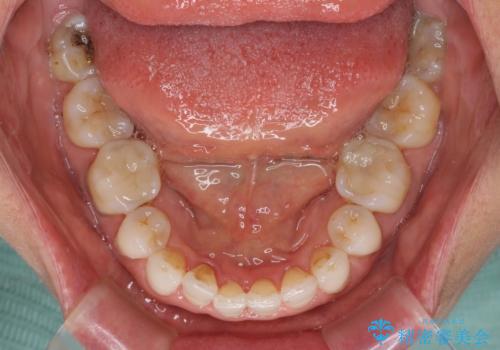

矯正治療の後戻り インビザライン・ライトでの再矯正

- 上下前歯を中心に、以前行った矯正治療の後戻りが気になるとのことで来院された患者様です。

後戻りは軽度であったため、インビザライン・ライトにて治療を行うこととしました。

矯正治療後は、再度後戻りすることを極力回避するために、下顎前歯の舌側を細いワイヤーを用いて保定することとしました。